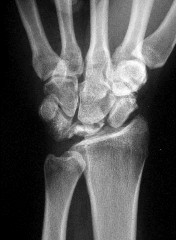

- الأشعة السينية (X-rays): هي الخطوة الأولى في تقييم الكسور، الخلوع، وتغيرات التهاب المفاصل. تساعد في تحديد مدى تدهور العظام والمسافات المفصلية. على سبيل المثال، تُظهر صور الأشعة السينية كسور السلاميات

. - الأشعة المقطعية (CT Scan): توفر صوراً تفصيلية ثلاثية الأبعاد للعظام، وهي مفيدة جداً لتقييم الكسور المعقدة، مثل كسور العظم الخطافي (Hamate Hook Fracture) التي قد لا تظهر في الأشعة السينية العادية